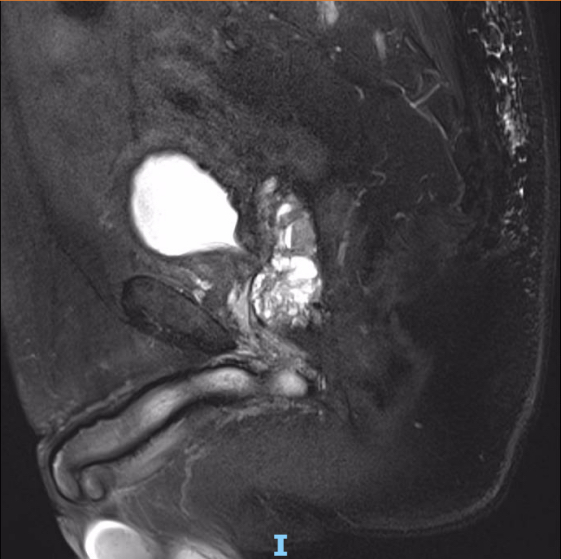

术后行各项指标随访监测,术前血色素137g/l,术后当天血色素123g/l,术后一周血色素127g/l。术前术后电解质情况稳定,无水中毒迹象。术后第六天复查尿流率10.5ml/s(尿流量142ml),超声提示“前列腺大小25x49x32mm(约21克),膀胱无残余尿”。术前PSA19.57ug/l,术后4个月复查PSA降至1.4ug/l。术后一年半余复查超声“前列腺大小28x41x30mm(约18g),膀胱壁毛糙,排尿后膀胱腔暗区消失”;MRI所示前列腺大小约20g(如下图所示);最大尿流率18.5ml/s(尿流量209.6ml)。